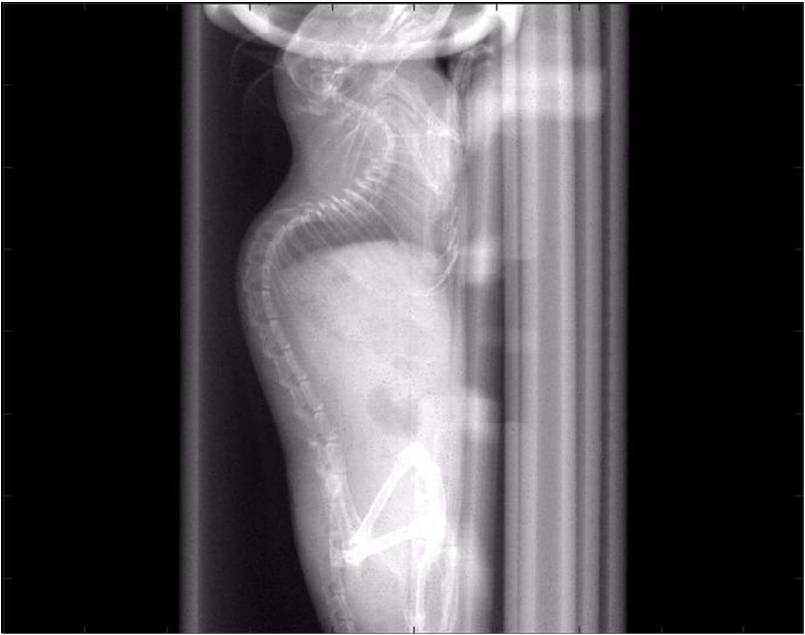

胸部和心血管的層析成像 胸部和心血管的3D圖像

心血管.jpg 心血管1.jpg